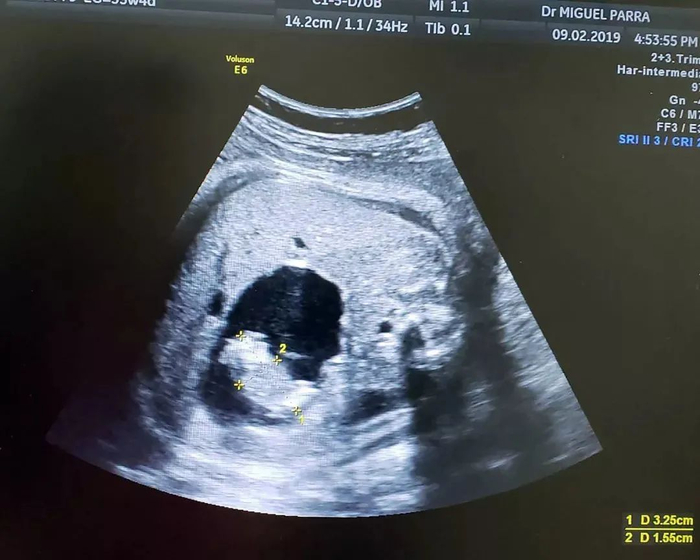

在彩超和3D/4D超声影像图上,帕拉·萨维德拉医生发现,图中充满液体的区域中,实际上含有一个非常小的胎儿;同时,还有一条独立脐带将小的胎儿连接在大的双胞胎的肠子上,并为小胎儿供血。

“我告诉了那位母亲,她的反应是——什么?不,这不可能!” 帕拉·萨维德拉医生说,“在我逐步解释后,她才明白。” 超声扫面的结果显示出位于子宫内的胎儿腹中,有一个正在成形的双胞胎小胎儿 | Dr. Miguel Parra-Saavedra